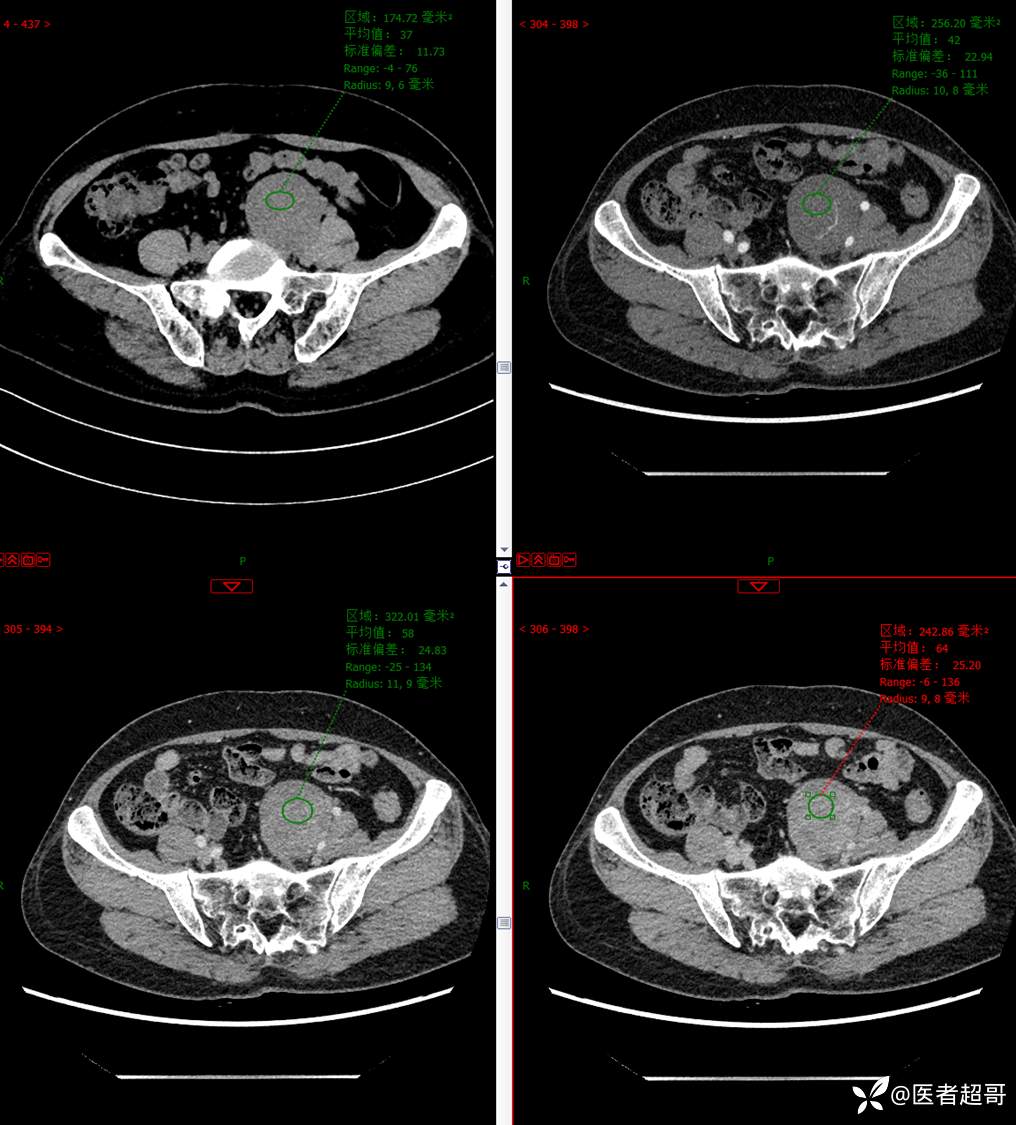

【影诊笔记559】查体发现右输尿管结石1周,发现腹膜后肿物,请分析,有病理!

•主 诉:查体发现右输尿管结石1周。

•现病史:患者1周前因小便不适来我院门诊行彩超检查提示右输尿管结石并右肾积水,伴腰疼,无血尿,无寒战,高热,患者求其进一步诊治,门诊以“右输尿管结石并右肾积水”收入院,患者自发病以来,神志清,精神可,饮食睡眠可,大便便秘,近期体重无明显增减。